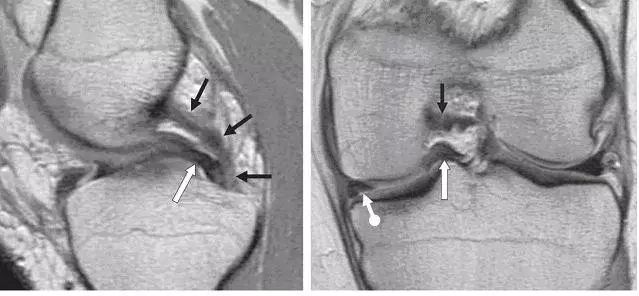

左图:外侧半月板,由于横截面面积一致,故在MRI 上可见外侧半月板前后角(纵向白色箭头)形状和大小较相似。上下腘肌半月板纤维束(黑色箭头)在外侧半月板后角处,形成裂孔,中间有腘肌腱(水平白色箭头)通过。右图:内侧半月板,可见后角(白色圆箭头),略大于前角(白色直箭头)